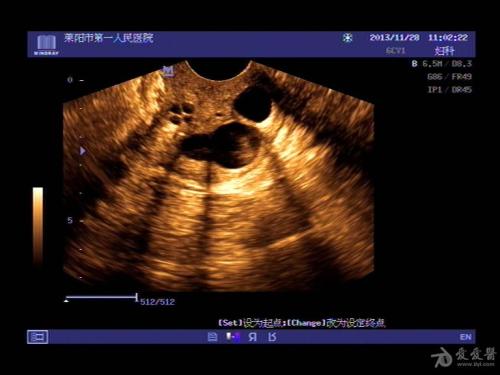

听小汪讲述了她的疾病,还有黄先生的疑惑,姜医生说:“宫颈囊肿是一种常见的慢性宫颈炎表现,专业上看,如果宫颈腺管受到周围组织的挤压从而使腺口发生阻塞,导致腺体内部的分泌物无法流出,从而潴留于腺体内,进一步促使腺腔扩张,导致大小不一的囊性肿物形成。宫颈囊肿一般是不会对生育有影响,但是如果子宫颈的位置形成来疤痕,就会对自然分娩产生影响。”

姜医生说:“宫颈囊肿的治疗要根据囊肿分散程度来选择不同的治疗方法,你的未婚妻卵巢囊肿较为分散,程度较轻,是不用治疗的。只要保持每年到医院进行检查,做宫颈涂片,观察囊肿的分散变化程度就可以了。”